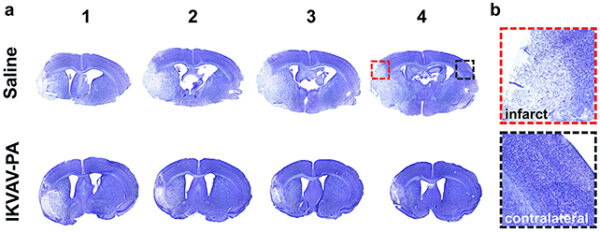

En comparación con los ratones no tratados, aquellos a los que se les administró el biomaterial inyectado después de la restauración del flujo sanguíneo al cerebro mostraron menos daño al tejido cerebral, menos signos de inflamación y menos signos de respuestas inmunes dañinas. La función principal de IKVAV-PA es estimular la reparación de las células nerviosas tras una lesión, a la vez que minimiza la inflamación. Esta inflamación representa un riesgo real, ya que el cuerpo continúa reaccionando al bloqueo inicial del flujo sanguíneo.